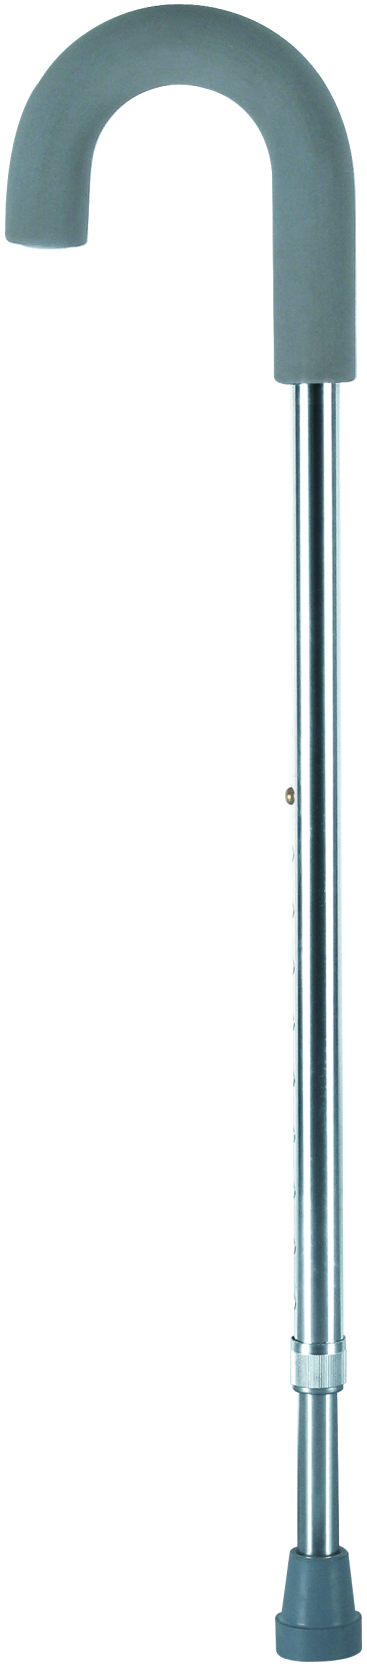

- Crutches

Crutches are an important medical rehabilitation AIDS, branch cane, elbow crutches, axillary crutches, multi-foot crutches, crutches play an important role in walking, not only to provide support and balance, but also to help improve gait and reduce energy consumption